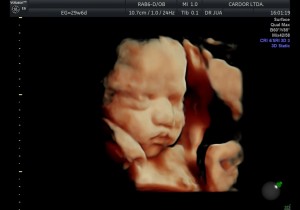

En el último trimestre del embarazo, entre las semanas 28 a 40, el bebé se prepara para nacer.

Vea la siguiente presentación. Imágenes 100% Cardor: